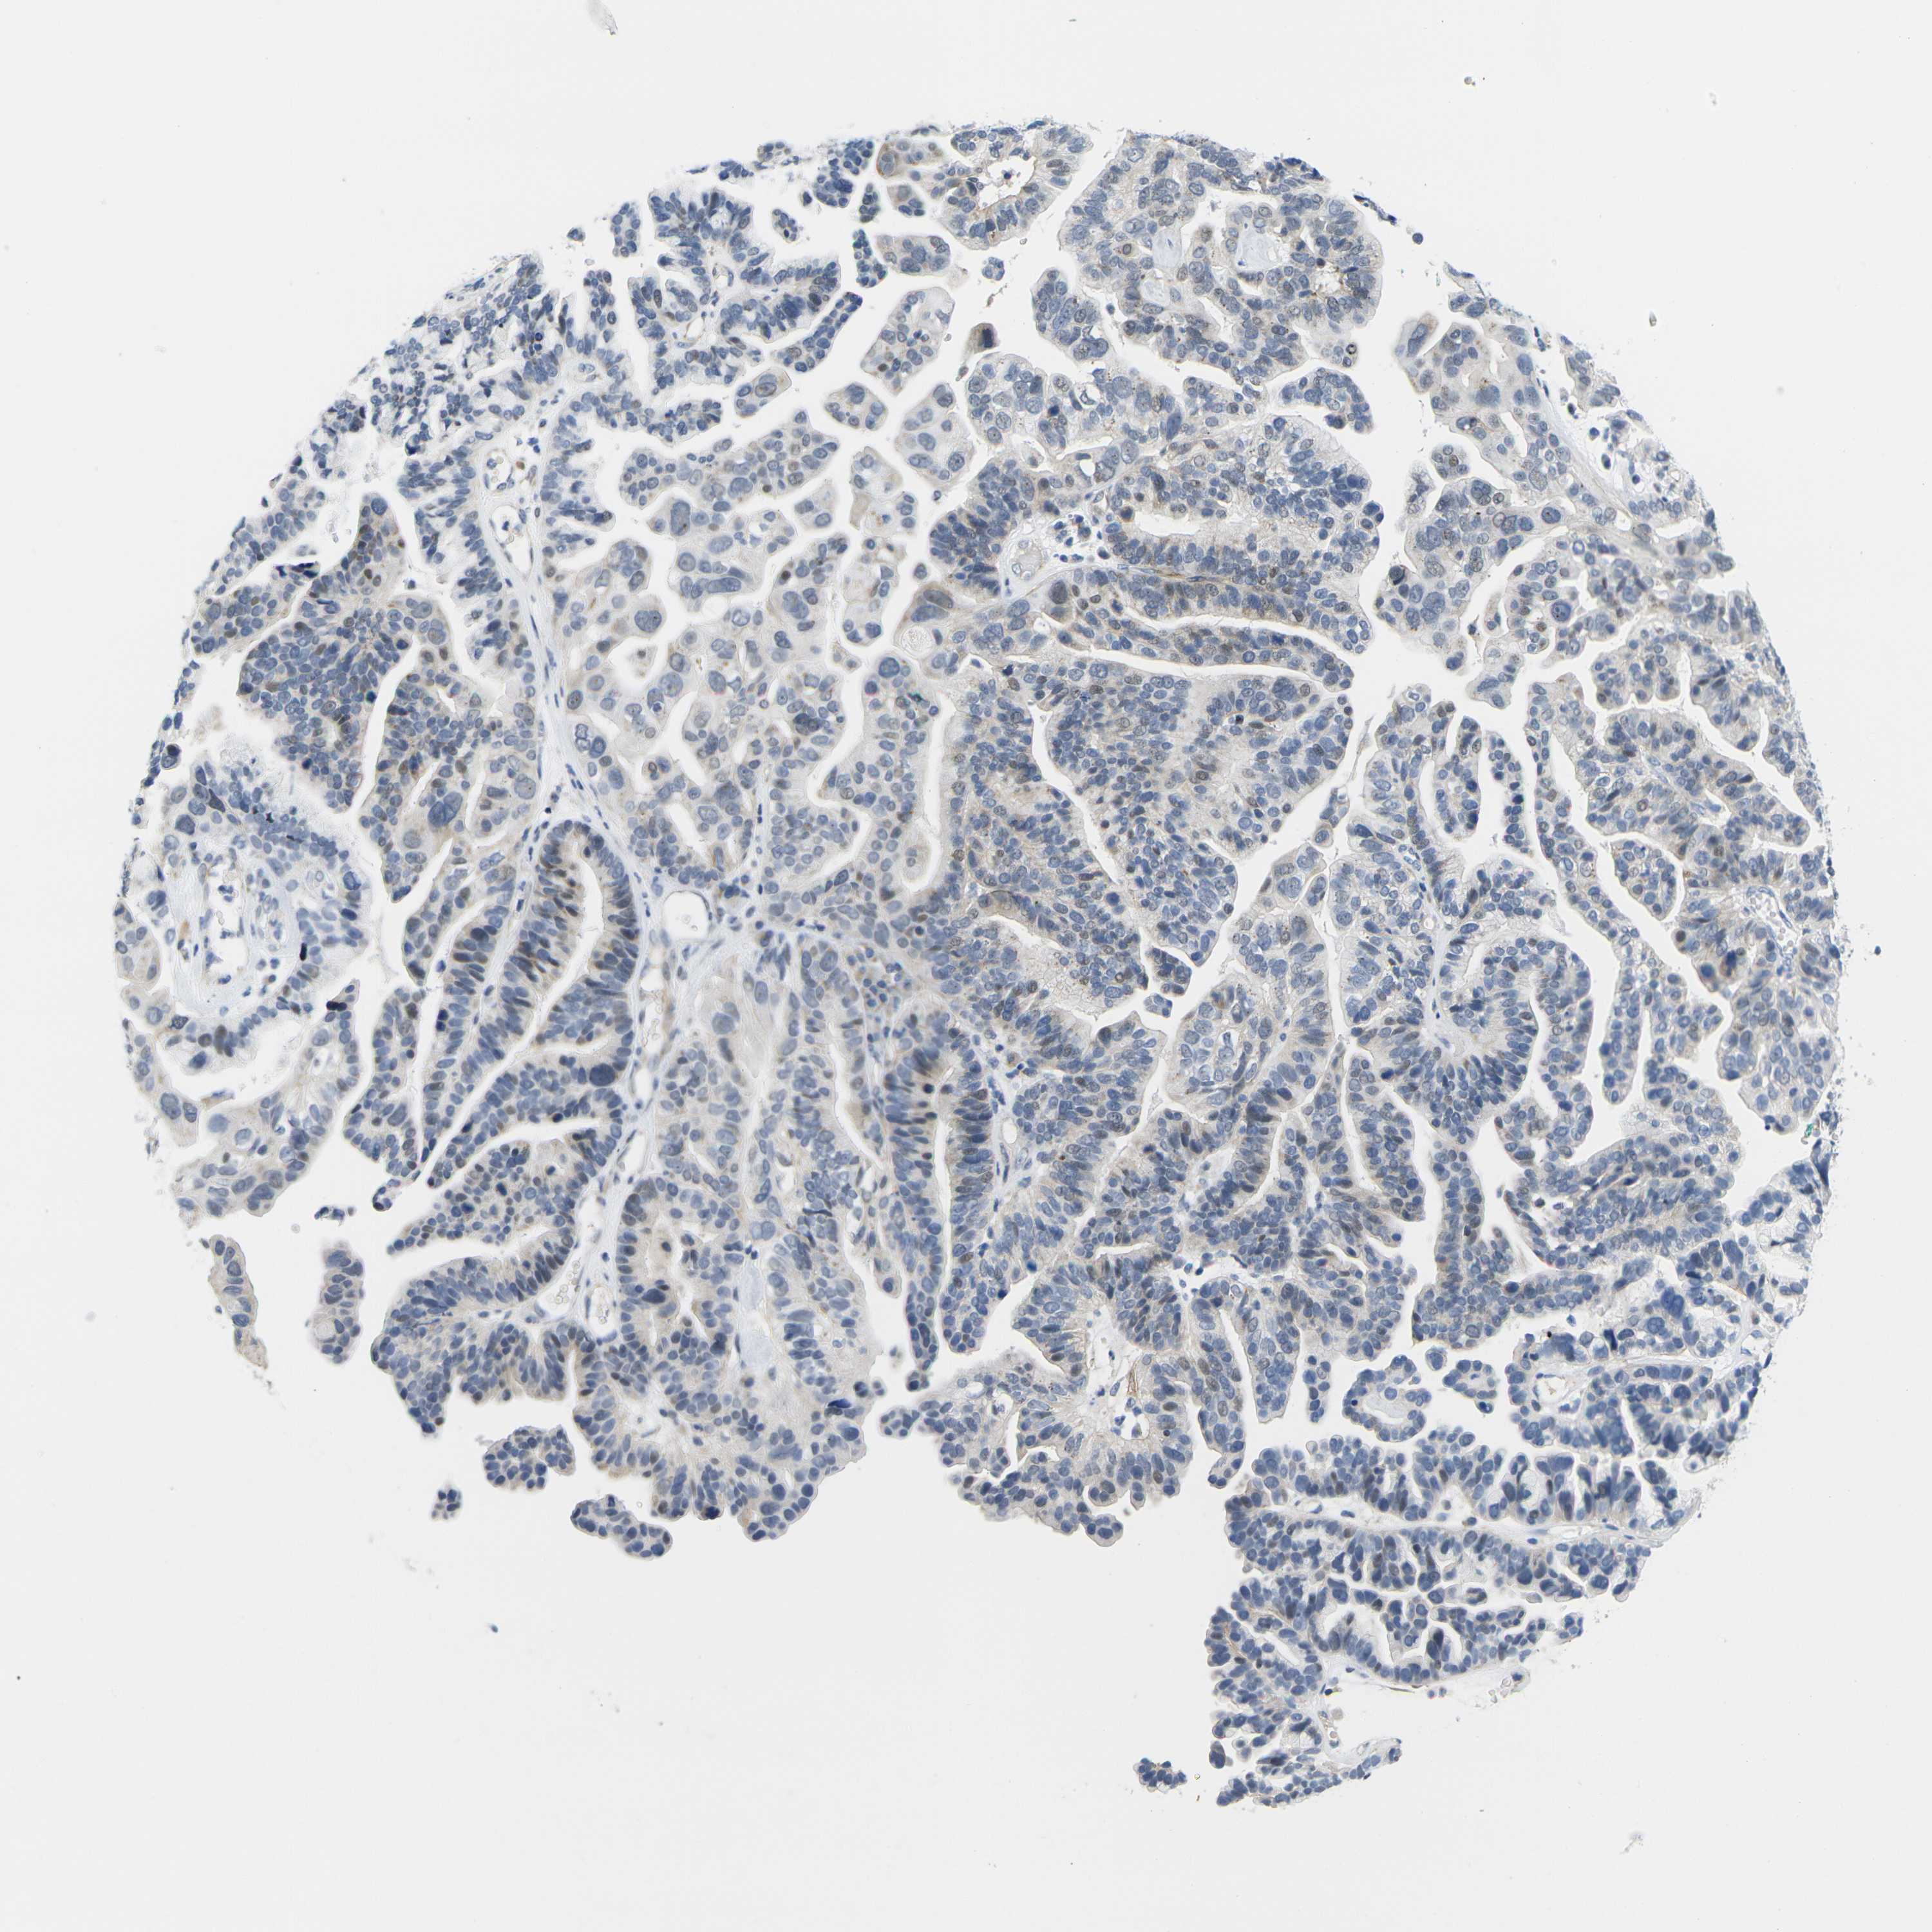

OVARIAN CANCER - Protein expressioni

A mouse-over function shows sample information and annotation data. Click on an image to view it in a full screen mode. Samples can be filtered based on level of antibody staining by selecting one or several of the following categories: high, medium, low and not detected. The assay and annotation is described here.

Note that samples used for immunohistochemistry by the Human Protein Atlas do not correspond to samples in the TCGA dataset.

Antibody stainingi

Antibody staining in the annotated cell types in the current human tissue is reported as not detected, low, medium, or high, based on conventional immunohistochemistry profiling in selected tissues. This score is based on the combination of the staining intensity and fraction of stained cells.

Each image is clickable and will lead to virtual microscopy that enables deeper exploration of all samples and also displays staining intensity scores, fraction scores and subcellular localization as well as patient and tissue information for each sample.

Antibody HPA012410

Staining

High

Medium

Low

Not detected

Intensity

Strong

Moderate

Weak

Negative

Quantity

>75%

75%-25%

<25%

None

Location

Nuclear

Cytoplasmic/membranous

Cytoplasmic/membranous,nuclear

Cystadenocarcinoma, serous, NOS

Carcinoma, endometroid

Cystadenocarcinoma, mucinous, NOS

Carcinoma, NOS